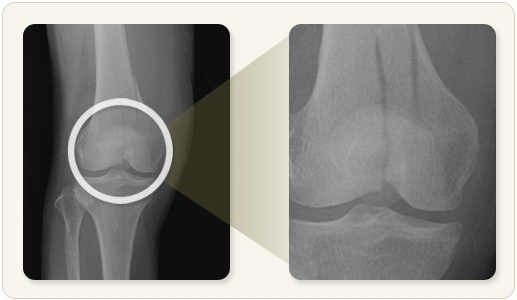

슬개골은 무릎 앞쪽에 위치한 뼈로, 강한 외상이나 낙상 등으로 골절이 발생할 수 있습니다. 수술로 고정한 이후 회복은 3개월 이상 걸릴 수 있으며, 회복 속도는 개인의 체력, 재활 순응도, 수술 방식 등에 따라 달라집니다. 최근에는 물리치료와 자가운동 프로그램을 조기부터 병행함으로써 회복을 앞당기는 사례가 늘고 있습니다. 따라서 단계별 관리가 무엇보다 중요합니다.